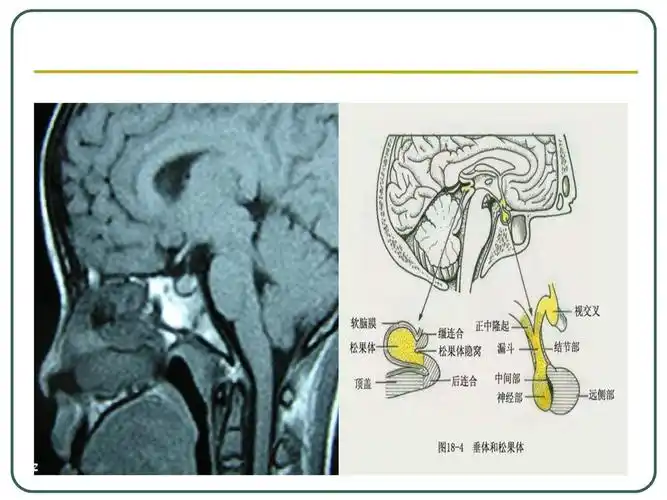

垂体的往世今生解剖标注详细

蝶鞍区 (1)垂体与垂体窝 hypophysis 位置 垂体窝 垂体

垂体磁共振影像解剖

垂体的解剖和功能 大小:0.5×1×1cm 重:0.5~0.